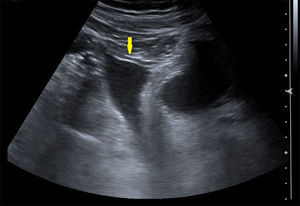

La ecografía puede indicar el diagnóstico, mostrando una masa hiperecoica ovoidea3,7,8, pero es la TAC la herramienta diagnóstica fundamental, ya que permite no solo descartar otras causas de abdomen agudo, sino realizar el diagnóstico de certeza. Se presenta como una lesión de densidad grasa mayor de 3cm, de bordes mal definidos y con imágenes lineales finas en su interior de mayor densidad, generalmente medial al colon ascendente o anterior al tranverso3,6–8.

Pese a la analgesia administrada, el dolor persiste, por lo cual se solicita ecografía abdominal, donde se objetiva líquido libre sin otro hallazgo patológico. Se decide realizar TAC, con la que se llega al diagnóstico definitivo de infarto omental.